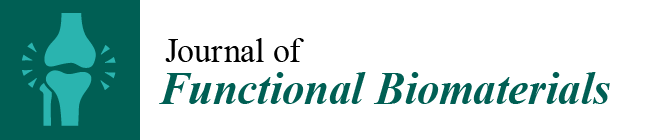

3.1. Intact and Minced Collagen Membranes: µCT Analysis

3.2. Intact Collagen Membranes: Histological Analysis